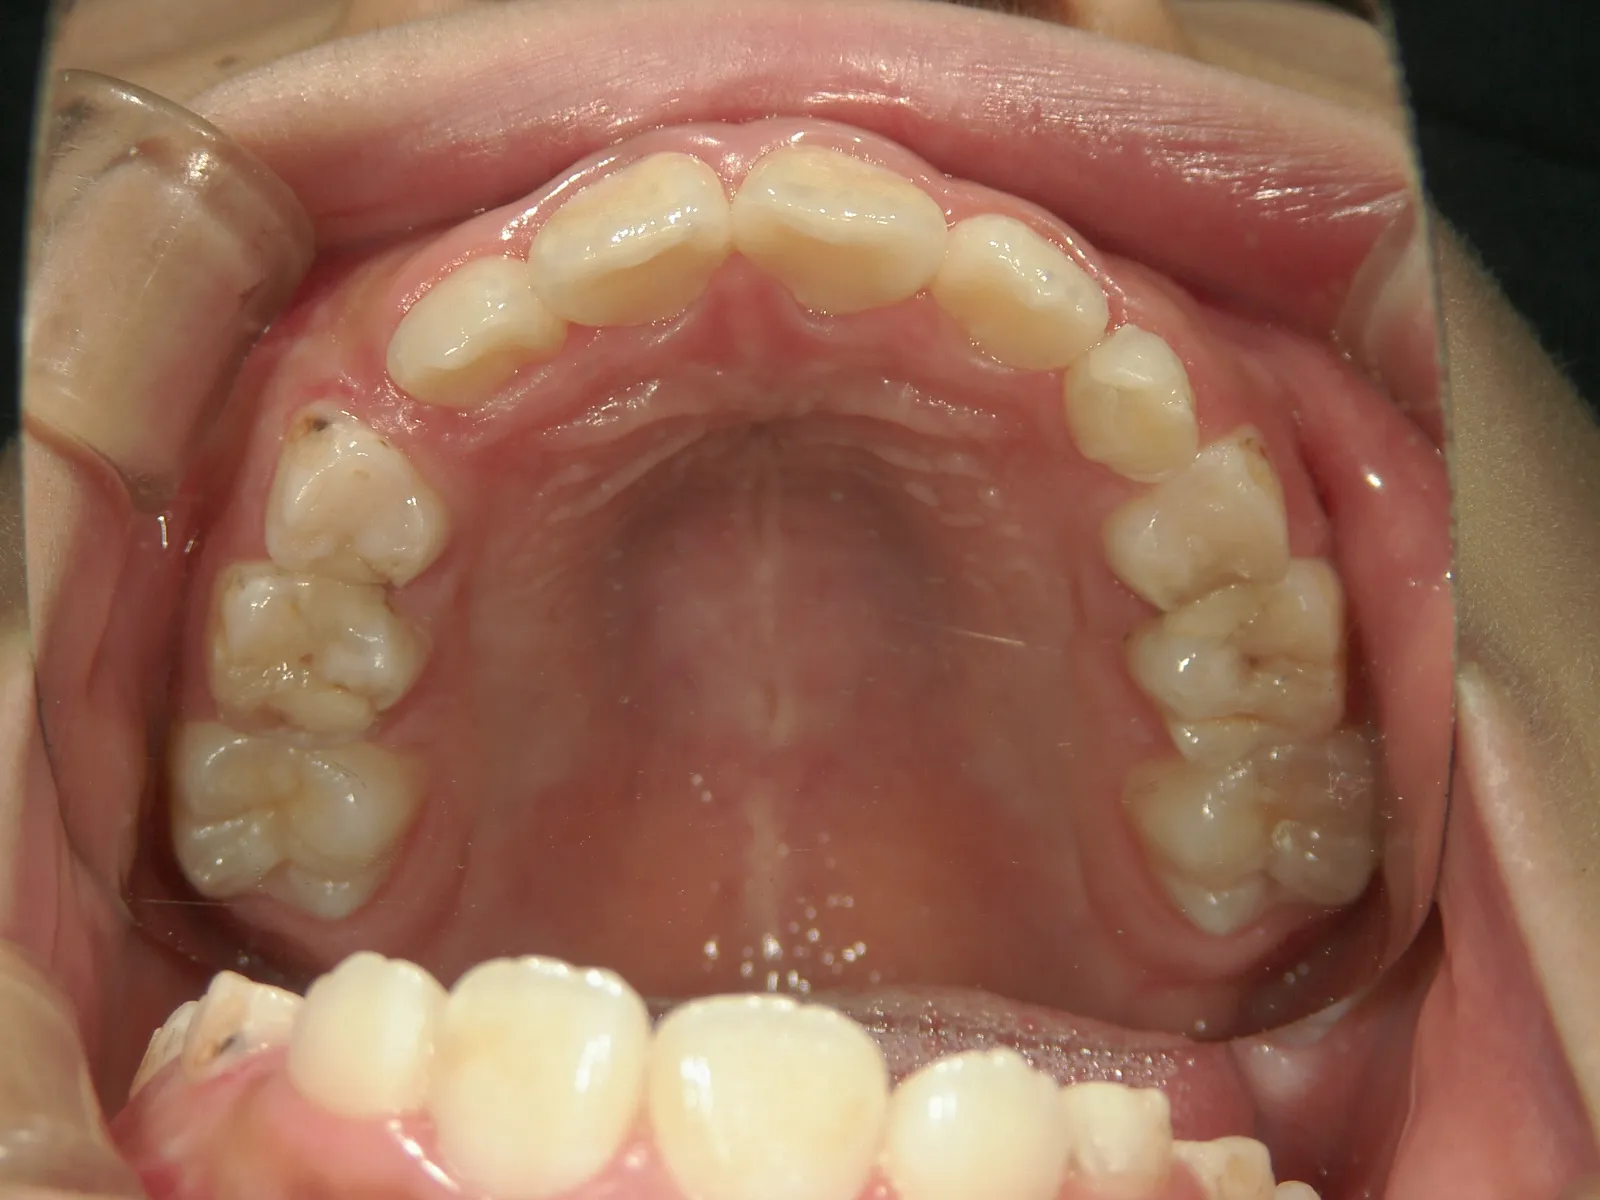

犬歯(3番目の歯)が生えてくるスペースがありません

連続抜去後